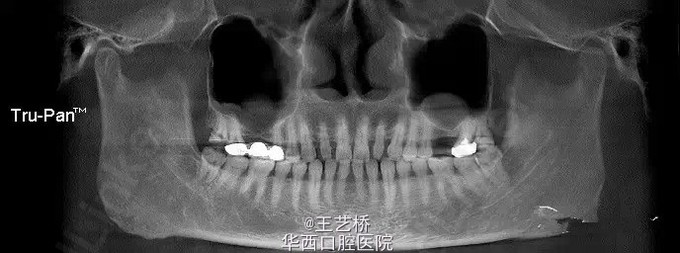

各式各样形态的上颌窦(二)

接着之前放图